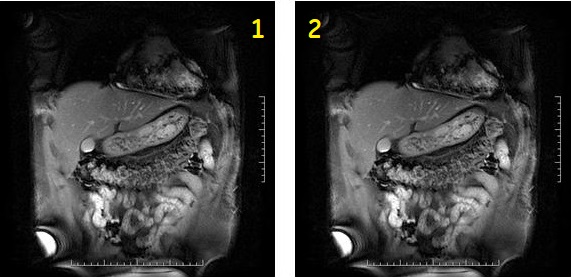

Table 1. Image legend Number Description 1 First phase 2 Second phase Figure 3. 2D Fat SAT Fiesta with 2 slices and MPH in interleave mode. 1 = 1st phase, 2 = 2nd phase

Table 2. Image legend Number Description 1 First phase 2 Second phase - Shim volume: 2D Fat SAT FIESTA is particularly sensitive to shim variations. Therefore it is always recommended to place a shim volume during the graphic prescription process.